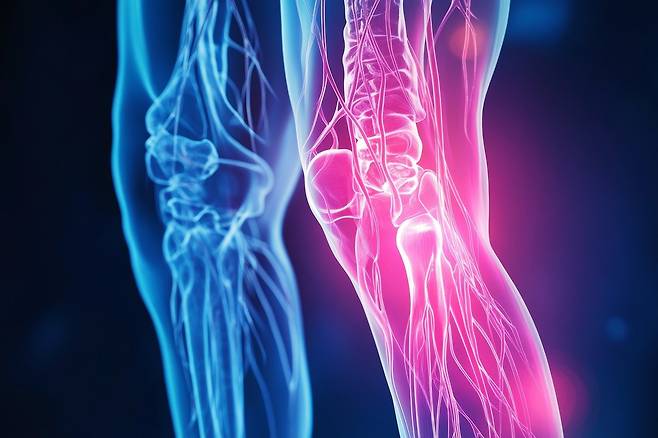

年齢を重ねるにつれ、理由もなく膝が痛んだり、腰がだるく感じる日が増えてくる。もしかして、自分は骨粗鬆症ではないかと心配になることもある。

多くの人が知らない事実の一つで、骨は夜により早く弱くなるということがある。今日は、夕飯で頻繁に食べるとカルシウムの損失を大きくする食べ物について見ていく。

私たちの骨は昼間よりも夜間に、より変化する。そのため、夜の小さな選択が骨の健康を左右する重要な基準となる。